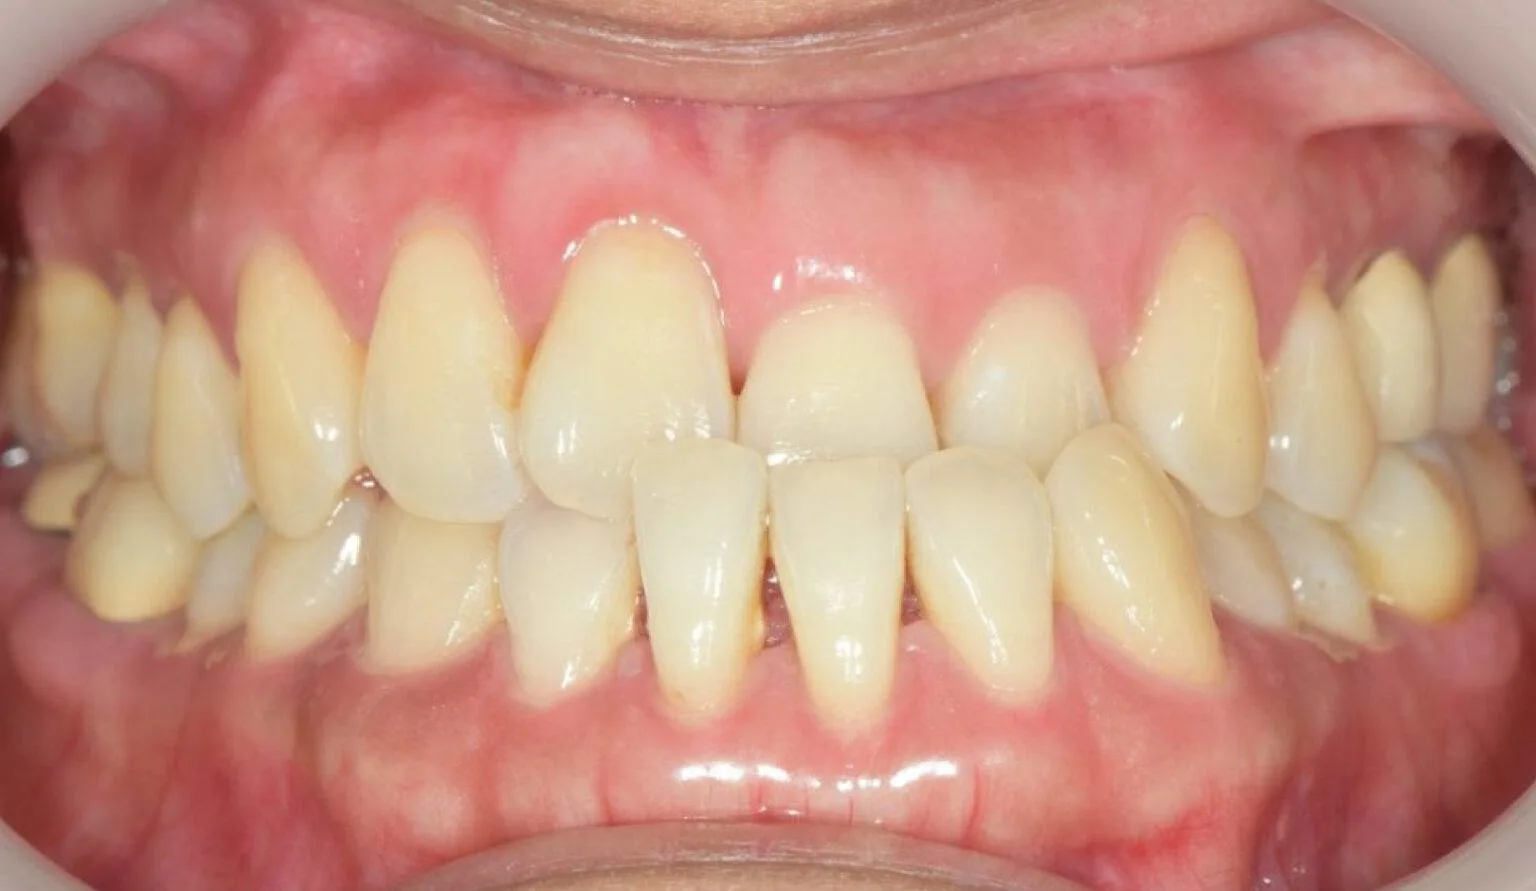

An open bite is a type of malocclusion (misalignment of teeth) where there is a gap or space between the upper and lower front teeth when the back teeth are closed together. This means that the front teeth do not make contact with each other when the mouth is closed, which can cause difficulty in biting and chewing food, speech problems, and jaw pain. Open bites can be caused by a variety of factors such as thumb sucking, tongue thrusting, genetic factors, or abnormal jaw growth.

Before open bite treatment showing misaligned front teeth at SmileBox Dental Clinic After open bite treatment showing improved alignment and bite at SmileBox Dental Clinic